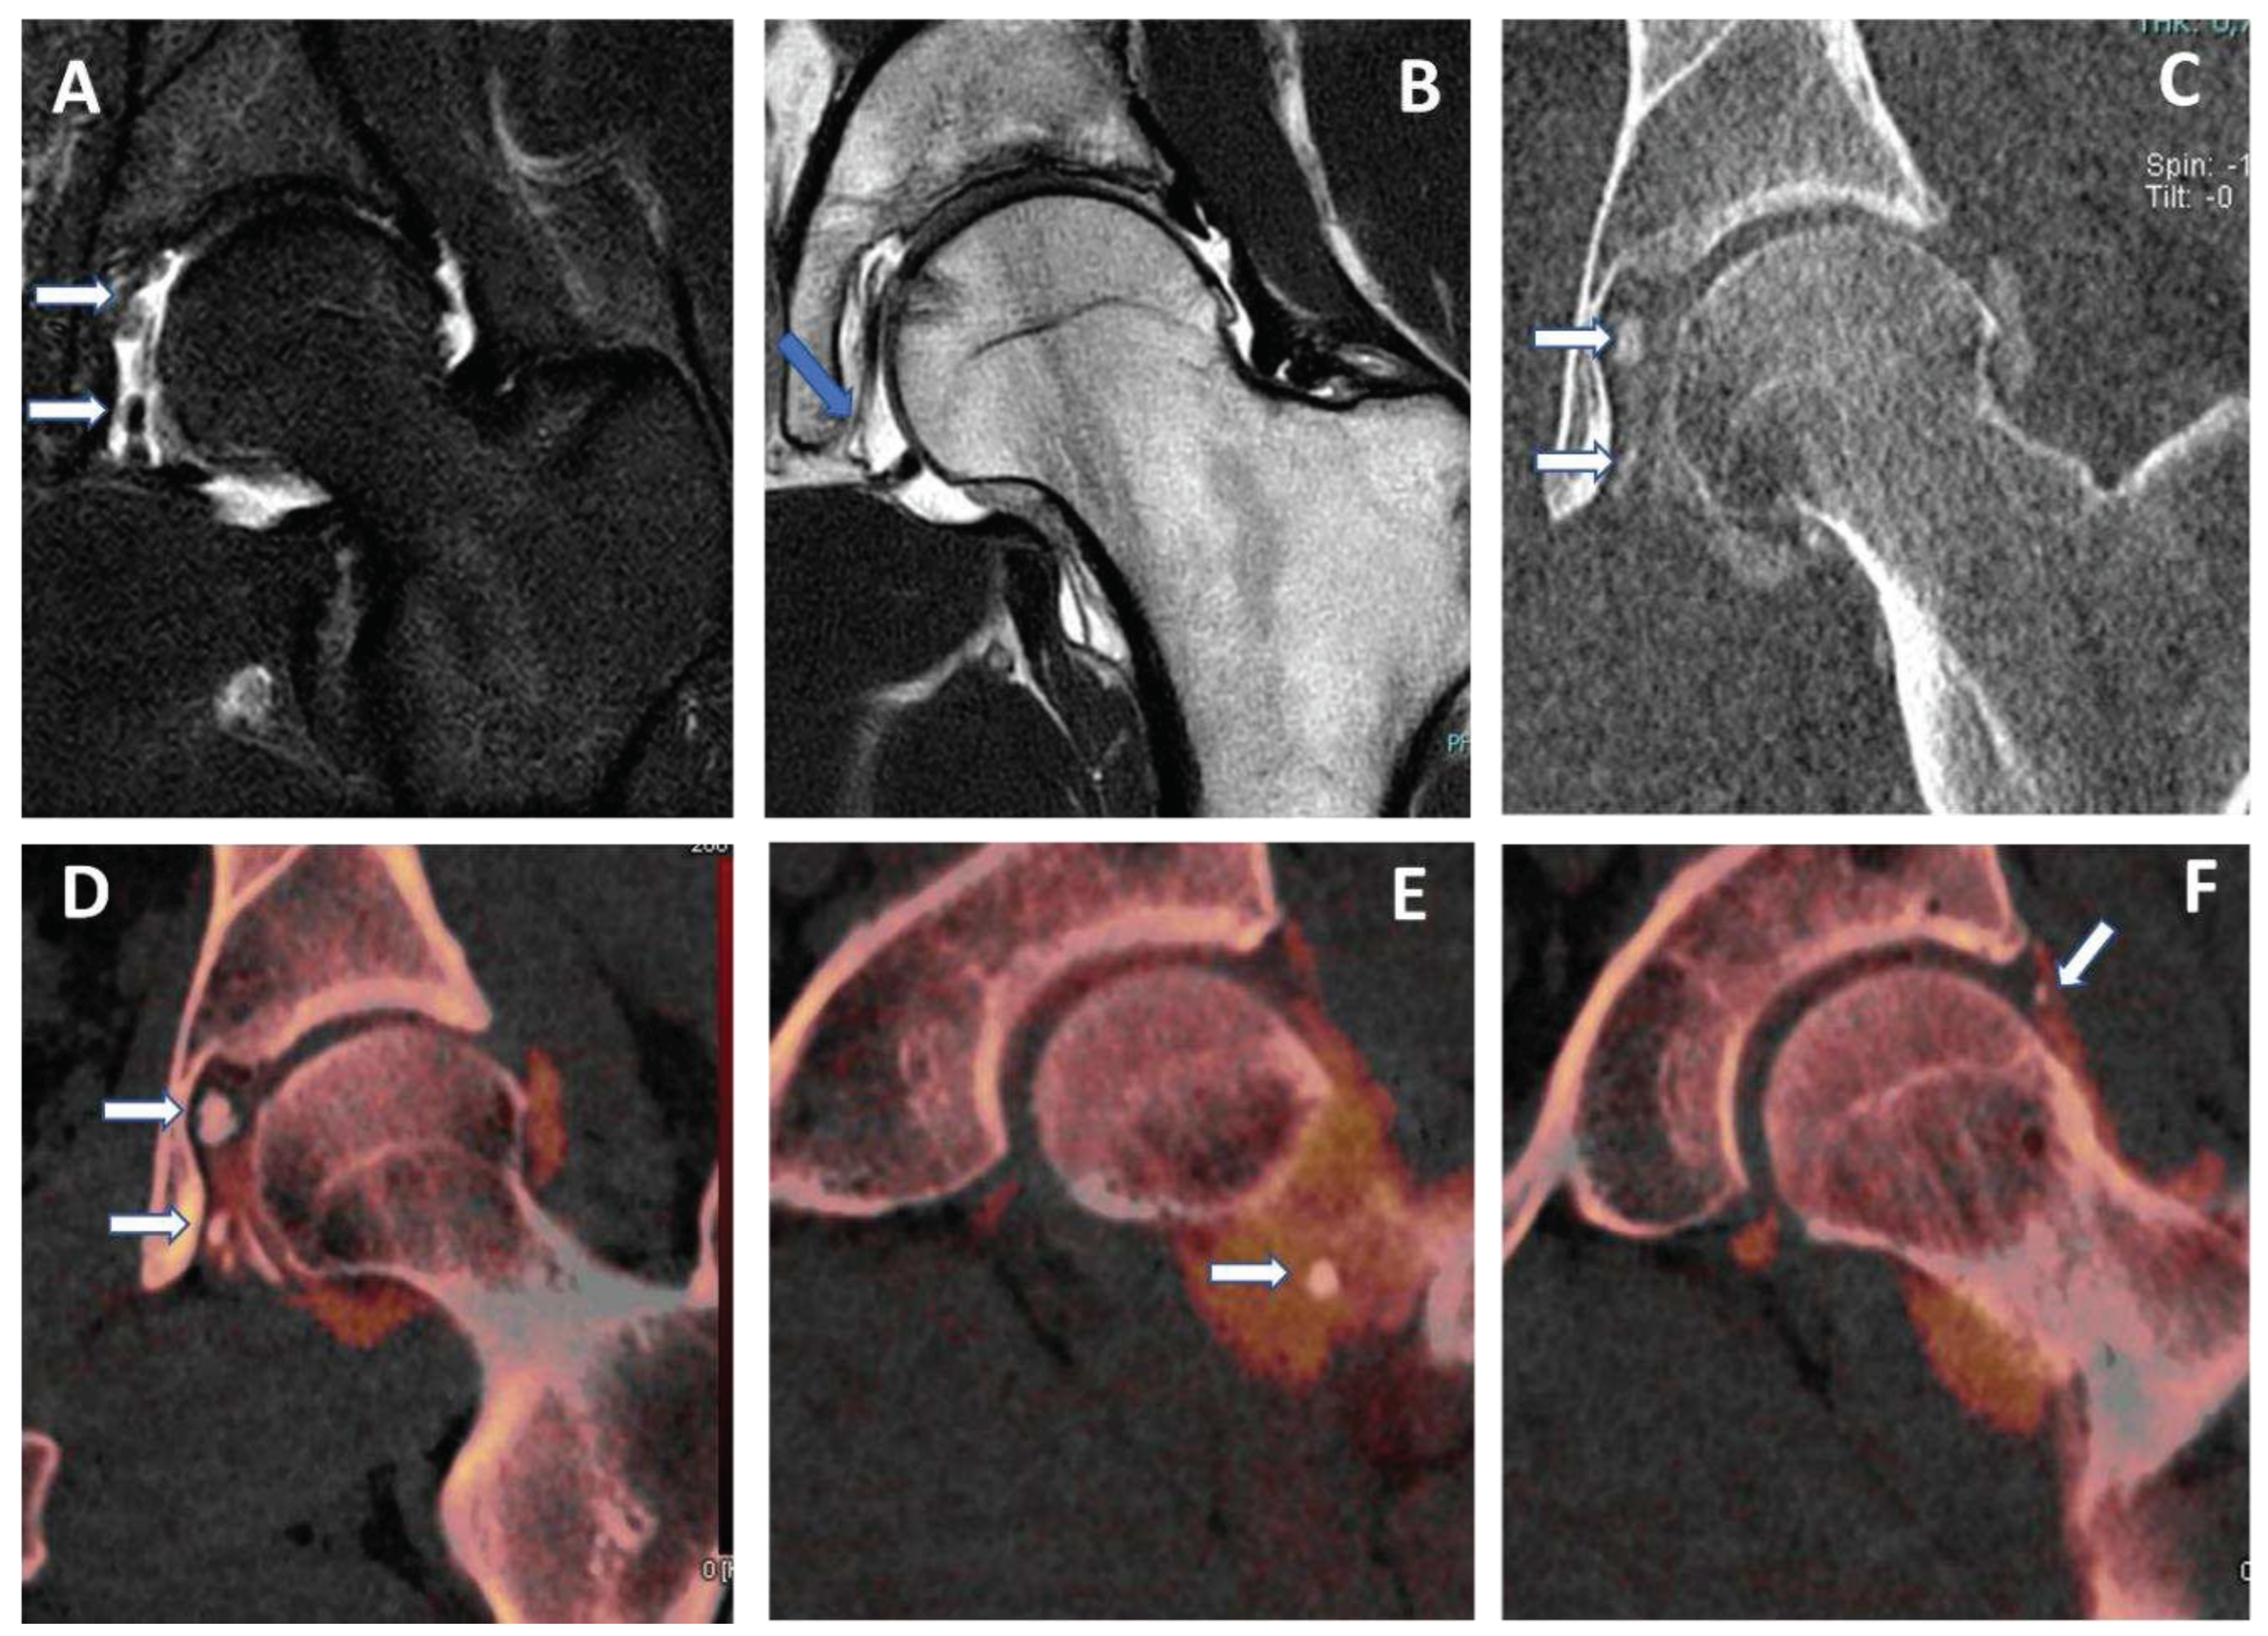

Figure 5. capsular, labral and loose calcifications in femoro-acetabular impingement. On MRA coronal STIR and T1 weighted images (A and B) is possible to recognize subtle filling defects (arrows on A) and capsular thickening (blue arrow in B). On DECTA VM I 1 mm coronal reconstructed image (C), calcifications are partially and erroneously subtracted (arrows). The corresponding DECTA iodine map images (D, E, and F), reconstructed on coronal plane (1 mm thickness), clearly show the presence of loose bodies, capsular and labral calcifications (arrows). .